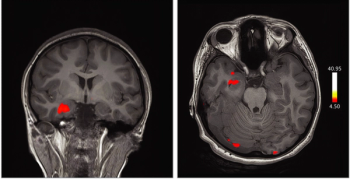

Large numbers of perivascular spaces seen in the brain are more commonly found in patients who go on to develop cognitive problems or dementia.

Images captured with fMRI in a case study reveal the role of the orbitofrontal cortex in patients infected with the virus who experience anosmia and ageusia.